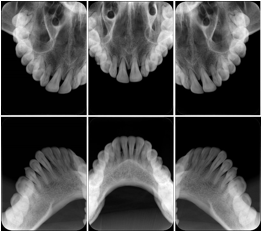

2. A patient requests cosmetic surgery to enhance their facial appearance. The case requires consultation between an orthodontist in New York and an oral surgeon in California. The cephalometric series of 2D projections constructed from a volumetric CT data set that is used for the discussion is arranged by a Structured Display for transfer between the two practitioners.

Cephalometric Series Structured Display

Figure OO-2. Cephalometric Series Structured Display